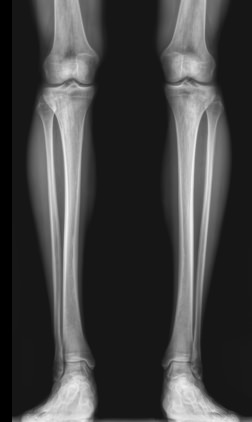

Большая берцовая кость ― вторая по толщине после бедренной ― вместе с малоберцовой образует часть нижней конечности ― голень. Она принимает на себя вес человека, позволяя ему свободно передвигаться и поднимать значительные грузы. Для повреждения голеней требуется значительная сила, какая встречается, например, при ДТП. С другой стороны, хронические патологии обеих костей, а также прилегающих к ним суставов, медленно и незаметно наносят не меньший вред, лишая мобильности.

При первых признаках заболеваний или травмы лучше проконсультироваться со специалистом и приступить к лечению на ранней стадии. Ортопед, травматолог или онколог направляют на рентген обеих голеней, если необходимо сравнить состояние симметричных участков, при травме или хронической патологии и при подозрении на аномалии развития. Выбор данного вида диагностики вызван простотой и доступностью методики, ее безболезненностью для пациента и высокой информативностью для врача.

Что покажет рентген костей голени обеих ног

• Изменения в мягких тканях: инородные тела, осколки, отеки;

• Патологии суставов, вошедших в снимок: вывихи и воспалительные процессы;

• Переломы костей: их расположение, уровень заживления и степень консолидации, соответствие сроку травмы;

• Состояние костной ткани: подозрение на онкологические изменения, остеопороз, остеосклероз, остеонекроз;

• Состояние надкостницы: истончение или утолщение.